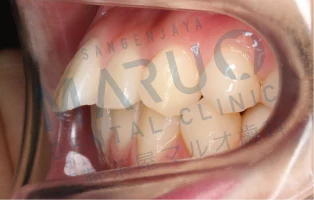

06.三軒茶屋マルオ歯科矯正担当医の治療例

症例1

治療前

治療中

動的治療終了時

| 主訴 | 上の前歯が前に出ている 歯のでこぼこ |

|---|---|

| 診断名 | 上顎前突 叢生 |

| 年齢 | 13歳 |

| 治療に用いた主な装置 | マルチブラケット装置 |

| 抜歯部位 | 上下両側第一小臼歯 |

| 治療期間 | 2年6ヶ月 |

| 治療費 | 92万4,000円(税込) |

| リスク、副作用 | むし歯や歯周病、歯根吸収、治療後の後戻りの可能性があります |